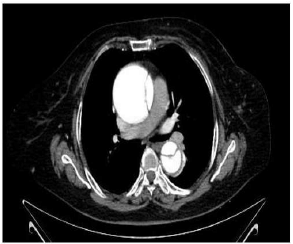

Homem de 57 anos, com antecedente de hipertensão arterial sistêmica, em uso de Clortalidona 25 mg, enalapril 20 mg 12/12 h e anlodipino 10 mg 1x dia, procurou o prontosocorro com queixa de dor torácica, “em rasgando”, de grande intensidade irradiando para dorso. O eletrocardiograma não apresentou alterações significativas. Realizou o exame reproduzido abaixo.